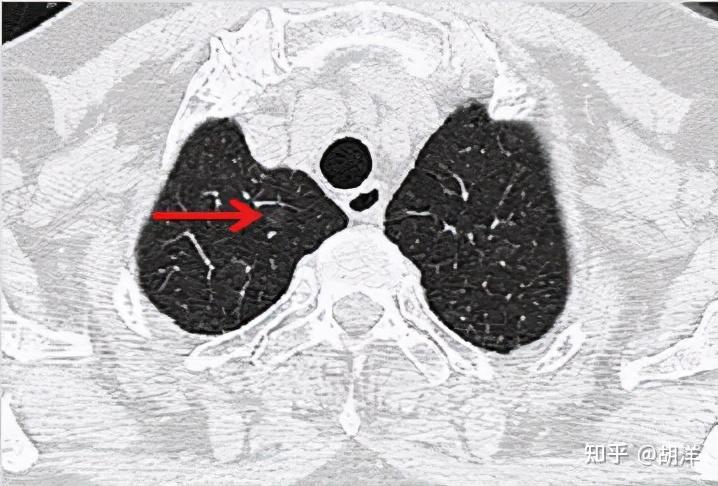

影像上的表现,原位腺癌应该是5-30毫米的纯磨玻璃结节,密度均匀,CT值在-600以下,极少有空泡、毛刺、胸膜牵拉和分叶,可以有血管穿行,但无血管弯曲。当然若病灶在10毫米以上时,诊断原位腺癌要慎重,因为1厘米以上的病理上是原位腺癌的少见。

看着,非常不错,以后原位腺癌与非典型增生不是癌了,不需要手术了,至少不能按恶性肿瘤的方式进行手术了。这是好事!但真的到了临床上,如何把握,我看仍是前路漫漫,迷雾重重!我们先举几个例子,来看看影像上如何来区分AAH、AIS、MIA以及浸润性腺癌。下面的四幅CT图分别各是其中的一种,是我们术后有病理依据确诊的病例,你能分出哪张是哪种吗?

有没有高手能分辨出来?我是一头雾水,根本分不清到底哪个是哪种。都是纯磨玻璃结节,都是瘤肺边界清楚,大小都在1厘米左右或以下。现比如下面这四幅CT图也是分别为AAH、AIS、MIA以及浸润性腺癌(贴壁型),你能分得清楚哪幅图是哪种吗?

这几乎就是四胞胎,长的没什么区别,但病理类型天差地别。现在把AAH与AIS剔除出恶性肿瘤后,更是差别巨大了,是癌与非癌的区别了,但没有手术切除病检的情况下,你如何来区分?